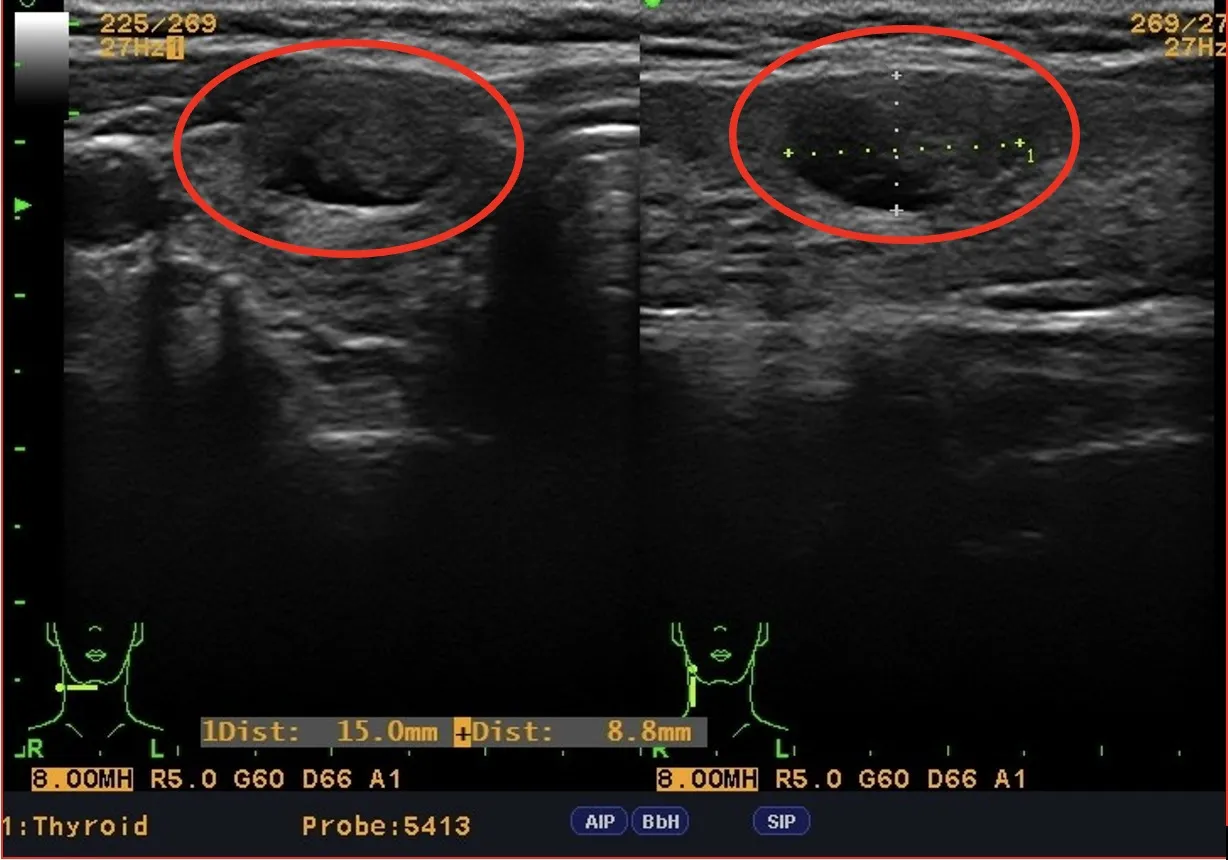

最近一位45歲女性因最近覺得脖子腫,❗️喉嚨有異物感❗️,合併聲音沙啞❗️而來求診,除了懷疑胃食道逆流的疾病外,陳醫師也進一步安排👨‍⚕️甲狀腺的檢查。

🩻甲狀腺超音波意外發現:右邊甲狀腺有一顆1.5x0.9公分的結節,雖然超過九成的甲狀腺結節是良性的,但是我們還是安排患者做進一步甲狀腺細針抽吸細胞學檢查。